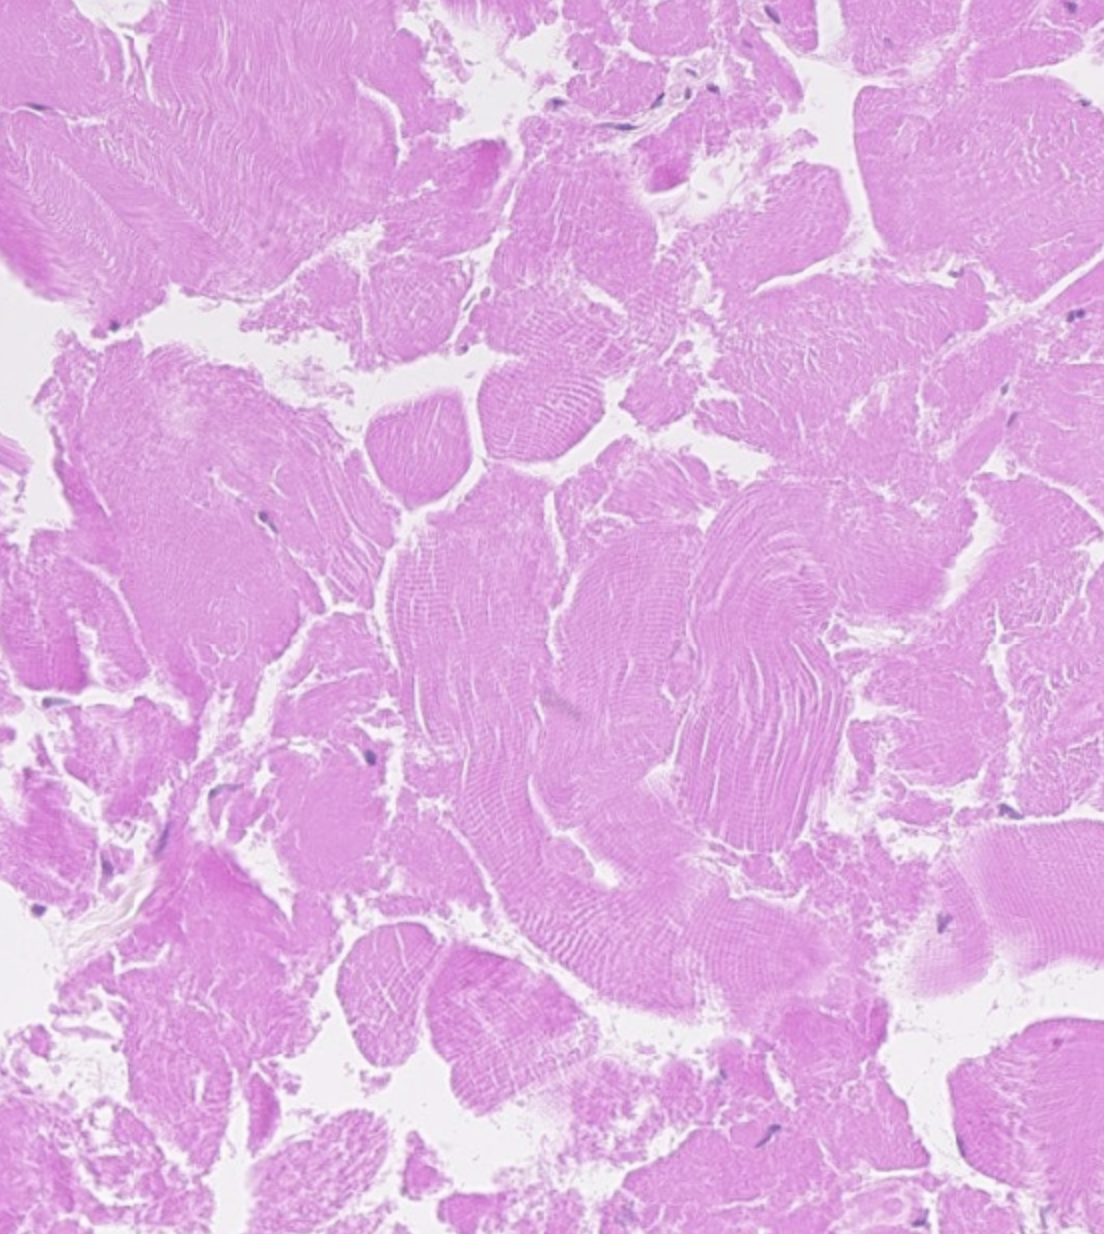

Wat voor type weefsel zie je hier?

A

Skeletspierweefsel

Q

Hoe kan je hartspierweefsel van skeletspierweefsel onderscheiden?

Hartspierweefsel heeft glansstrepen, en de locatie van de nucleus is anders